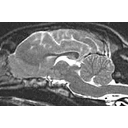

Canine Brain MRI.jpg